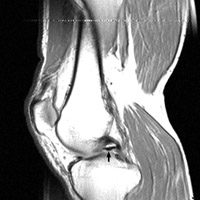

Fragment-in-Notch Sign

Bucket-handle tear of the menisci

The displaced fragment of a bucket handle tear of the meniscus can move medially to lie within the intercondylar notch. The fragment-in-notch sign is defined as a band like area of low signal intensity within the intercondylar notch, not appearing on the same slice as the PCL. The sign, when identified, can be valuable in picking up a bucket handle tear of the meniscus.

- Click on the image for a larger versionA - Click on the image for a larger versionB